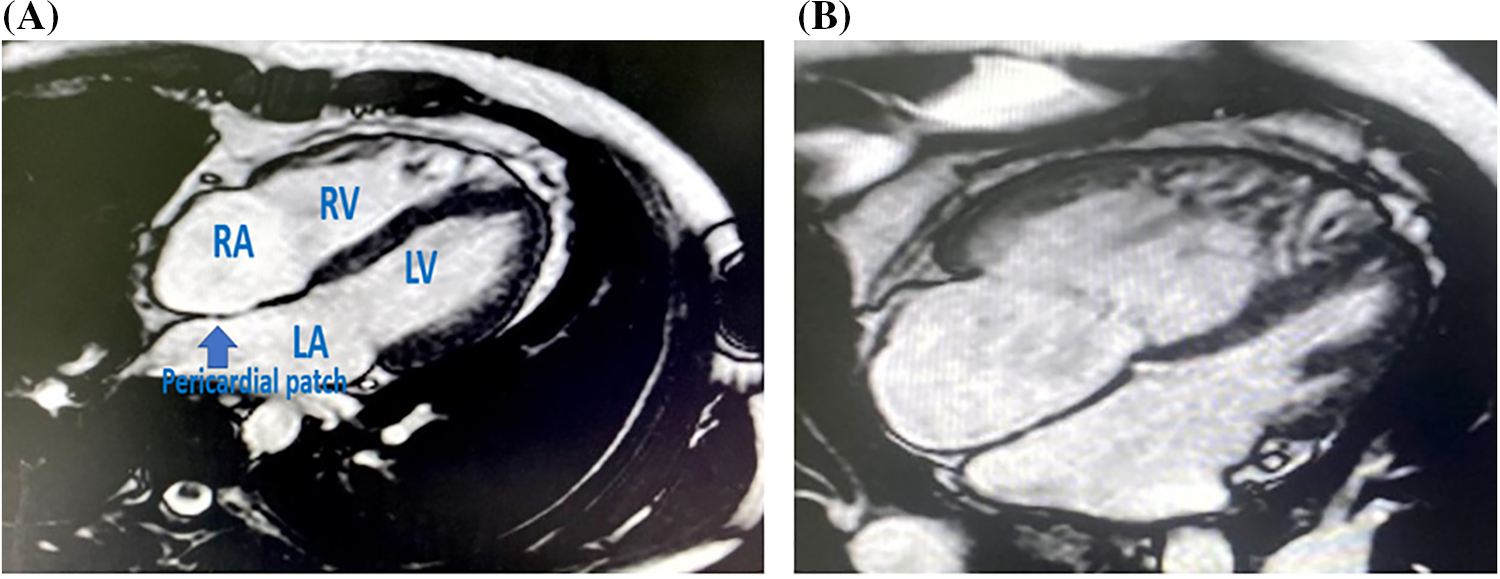

The transcatheter arm had more reverse remodeling with significant difference with the surgical arm (p-value 0.03 for indexed RVEDV and 0.02 for indexed RVESV) (Table 3, Figs. 1 and 2).

Figure 1: SSFP 4 chamber MRI view in transcatheter closed case by ASO

Note: RA: right atrium, RV: right ventricle, LV: left ventricle.

Figure 2: (A) SSFP 4 chamber MRI view in surgically closed case by conventional method with reverse remodelling of RA and RV volumes. (B) SSFP 4 chamber MRI view in surgically closed case by conventional method with persistently dilated of RA and RV volumes

Note: RA: right atrium, RV: right ventricle, LA: left atrium, LV: left ventricle.